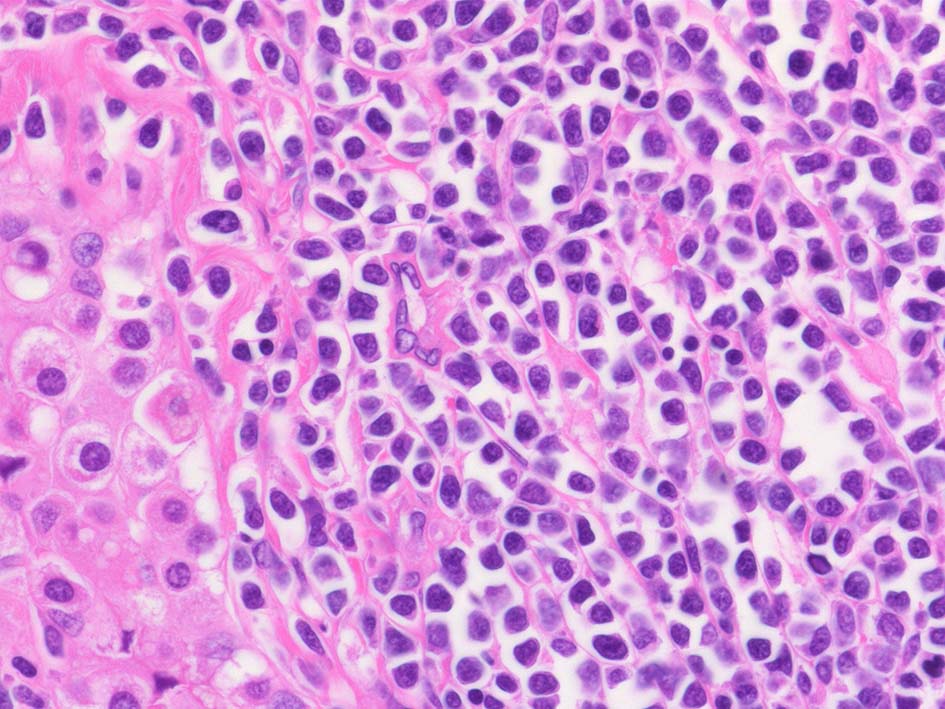

小リンパ球と同程度か1.5倍くらいのサイズ, round/ convoluted nucleiをもつリンパ球がシート状密に増殖する. 核クロマチンは粗で, 核小体が認められる核もある.

DLBCLとは細胞の大きさや細胞所見が異なっている. 精細管への浸潤, 占拠所見がある.